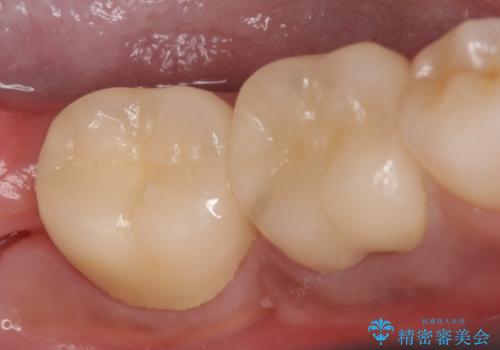

再根管治療終了後、オールセラミッククラウンによる補綴を行いました。

今回用いたオールセラミッククラウンはジルコニアフレームという白い素材の上にセラミックを盛っているため、審美性が非常に高いのが特徴です。

また、ジルコニアは人工ダイヤモンドの材料にも使われているほど高い強度を持っており、そのためオールセラミッククラウンは審美性だけでなく、奥歯やブリッジの補綴も可能とするクラウンです。